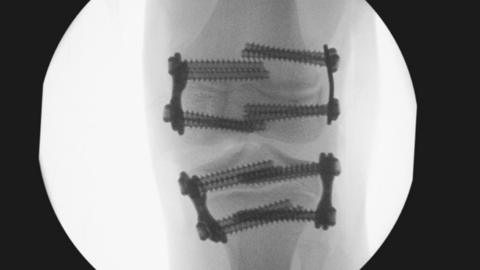

The patients were children when they were operated on by Kuldeep Stohr, and theirs are among 800 cases being reviewed by Cambridge University Hospitals NHS Foundation Trust (CUH) over concerns they fell "below expected standards".

The Department of Health and Social Care (DoH) said a national review would look at how complex orthopaedic surgery was overseen.